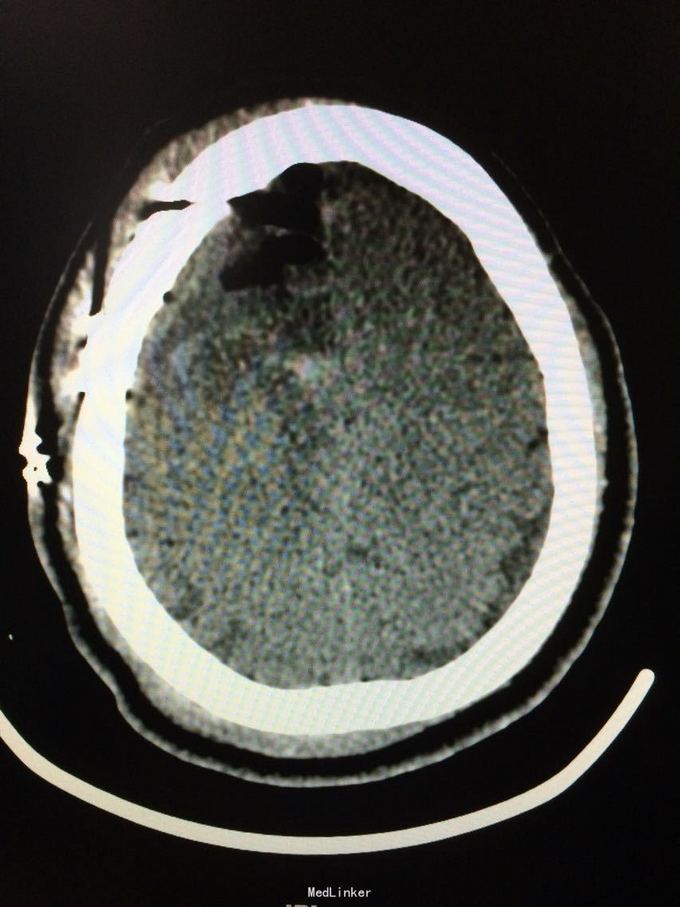

主诉:记忆力减退3月,左侧肢体乏力3天 病史:患者51岁女性,3月前无明显诱因出现记忆力减退,伴头痛,3天前出现站立不稳,左侧肢体乏力,步行困难,当地CT提示右侧额叶低密度灶,

查体:左侧上肢肌力4级,右侧5级,轻瘫试验左侧阳性 辅助检查:右侧额叶、胼胝体膝部病变伴出血,增强扫描明显强化。考虑胶质瘤

诊断:右侧额叶多发脑软化灶 处理:全麻下行右侧额叶占位病变切除术,术后病理提示:符合脑软化,未见明显肿瘤因素等